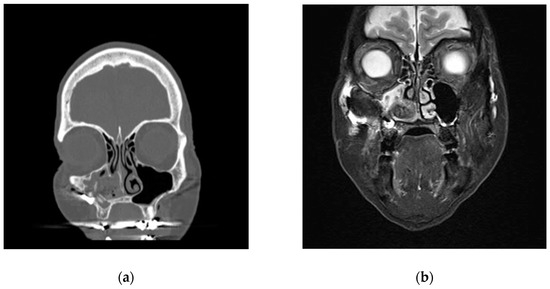

2. Case Presentation